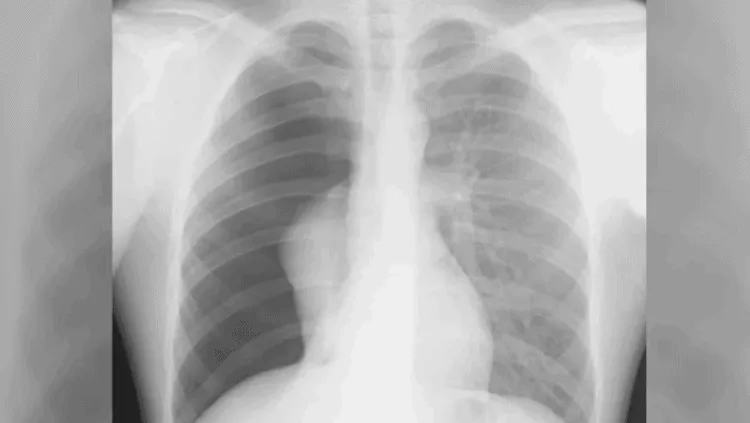

7. Triệu chứng khó thở hụt hơi do viêm phổi

Viêm phổi là tình trạng nhiễm trùng ở phổi do virus hoặc vi khuẩn gây ra. Trong đó, triệu chứng thở hụt hơi thường gặp ở người bị viêm phổi do virus, xuất hiện 1 – 3 tuần sau khi bạn nhiễm virus.

Bệnh viêm phổi làm cho đường thở của bạn sưng lên. Đồng thời, các túi khí trong phổi của bạn sẽ bị lấp đầy bởi các chất nhờn, dẫn đến khó thở, hụt hơi. Bên cạnh đó, bạn cũng có thể bị sốt, mệt mỏi, ho, ớn lạnh, đau đầu, chán ăn, buồn nôn.